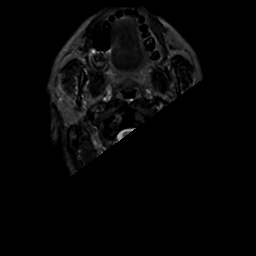

MR Study #10, April 28, 1991 -- Slice #0

[Home][Help][Clinical][Tour 1][Tour 2] Slice 0